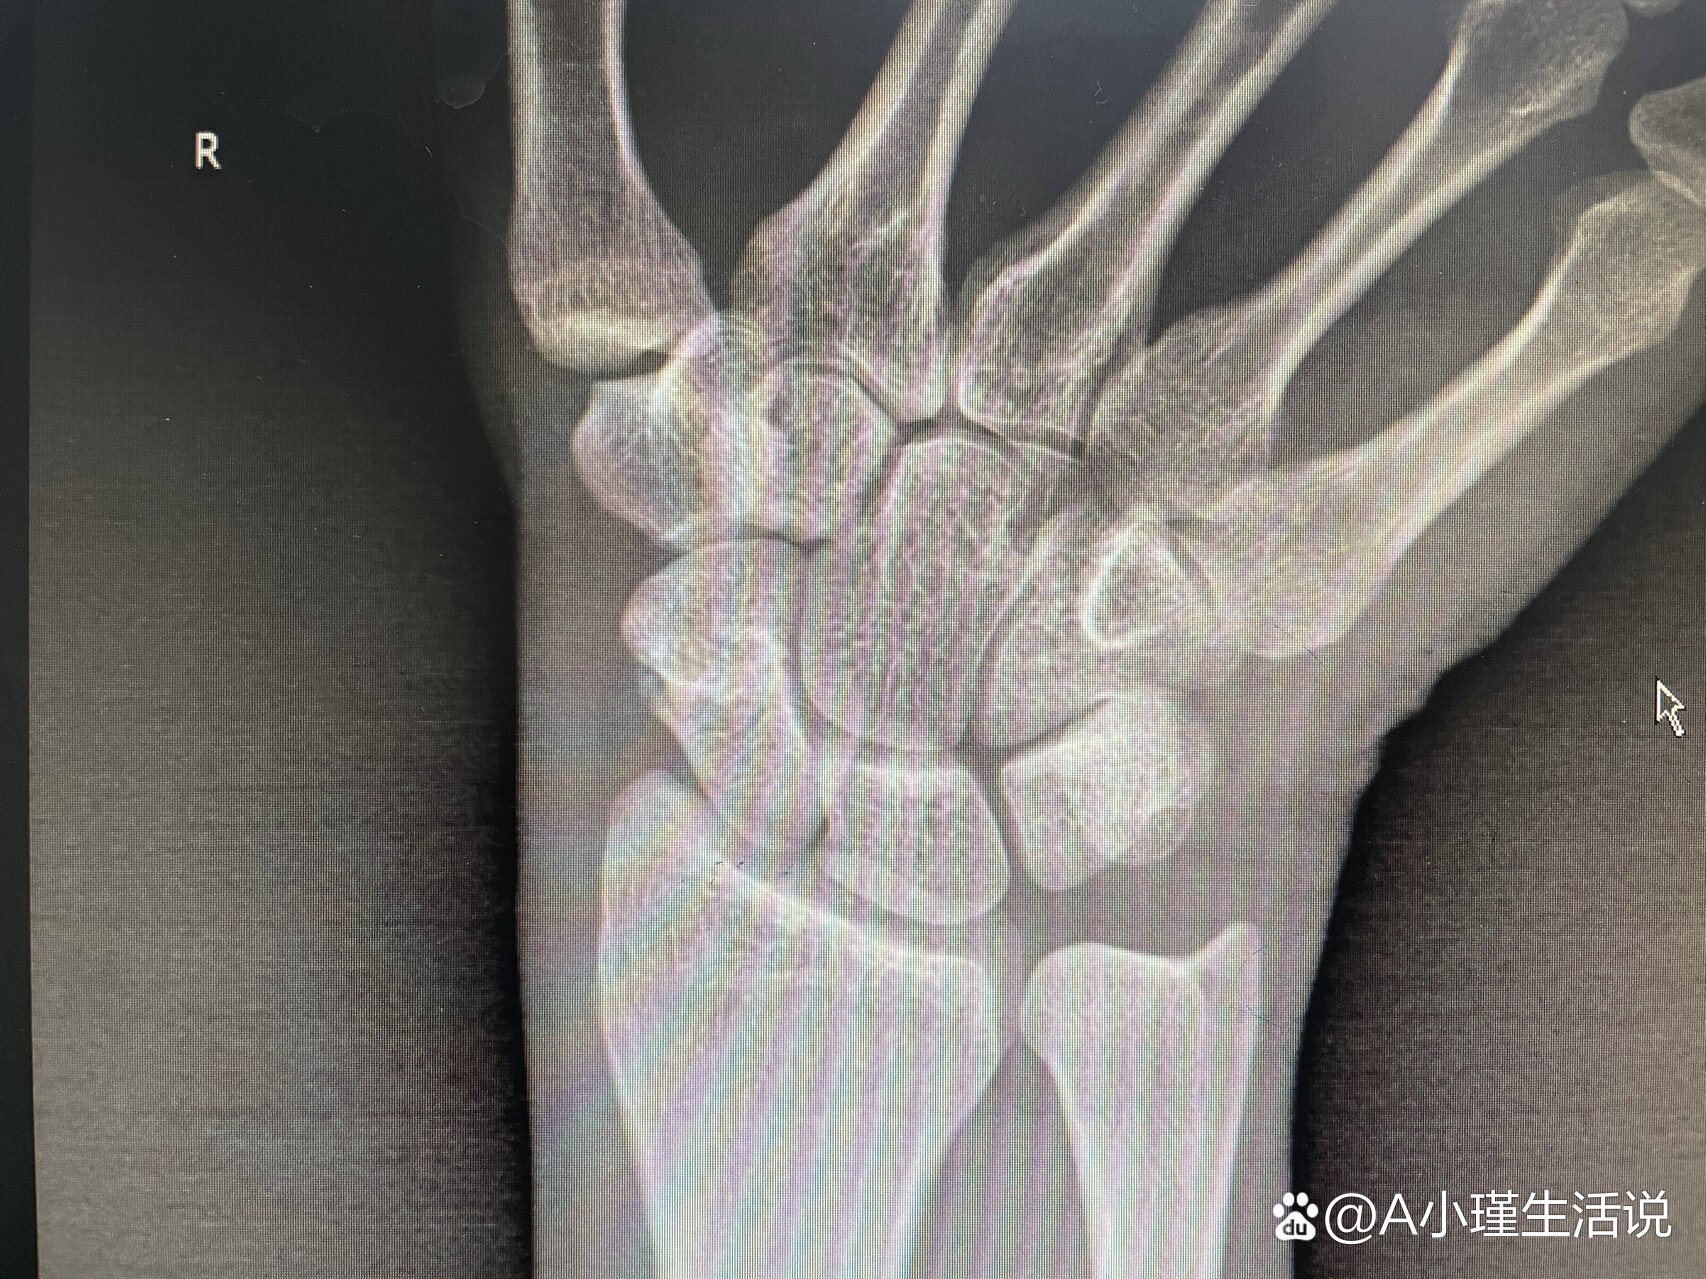

右踝关节脱位,舟状骨骨折,刚入院,无ct

图片尺寸432x576